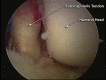

Posterior shoulder dislocation is an unusual injury often associated with electrical shock or seizure. As with anterior instability, patients frequently present with an impaction injury to the anterior aspect of the humeral head known as a "reverse Hill-Sachs lesion." The treatment of this bony defect is controversial, and multiple surgical procedures to fill the defect in an effort to decrease recurrence have been described. Most of the reports have focused on an open approach using variations of lesser tuberosity and subscapularis transfers, bone allograft, and even arthroplasty to assist with persistent instability. We advocate an arthroscopic technique that involves a suture anchor-based distal tenodesis of the subscapularis tendon or a reverse remplissage procedure.